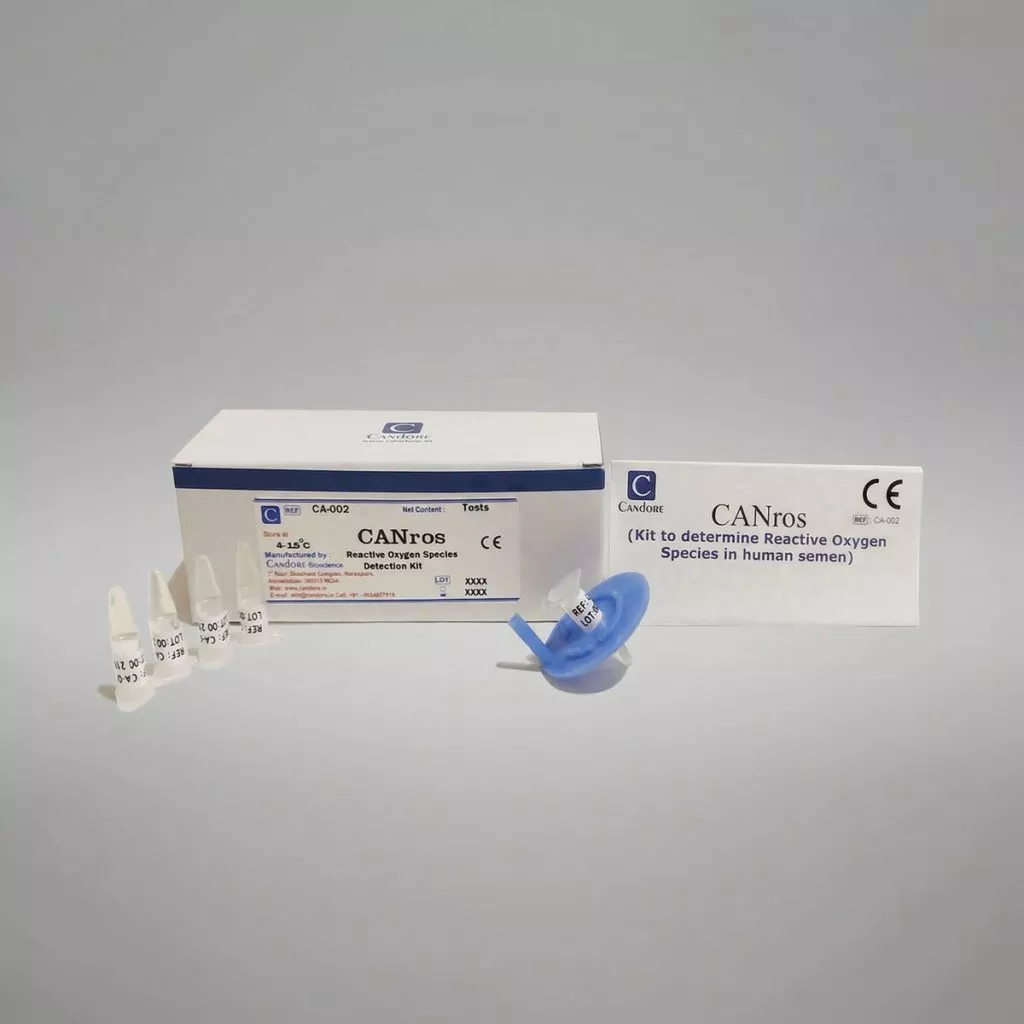

CANros